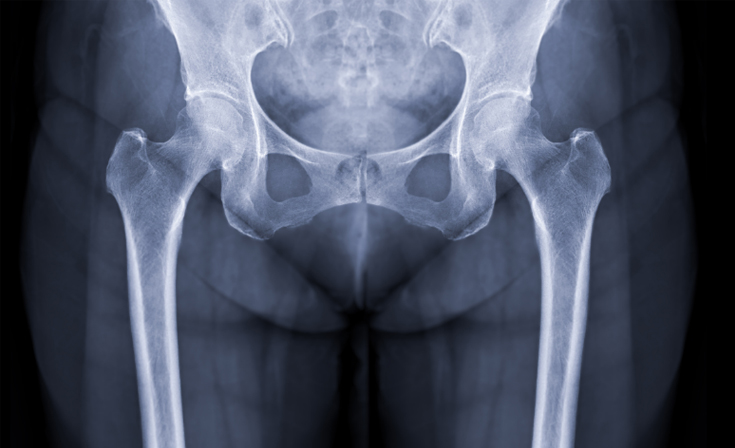

Hip

The hip joint is a ball-and-socket joint that connects the thigh bone (femur) to the pelvis, allowing for smooth and stable movement. While the hip is built for durability, injuries and degenerative conditions can significantly impact mobility and quality of life.